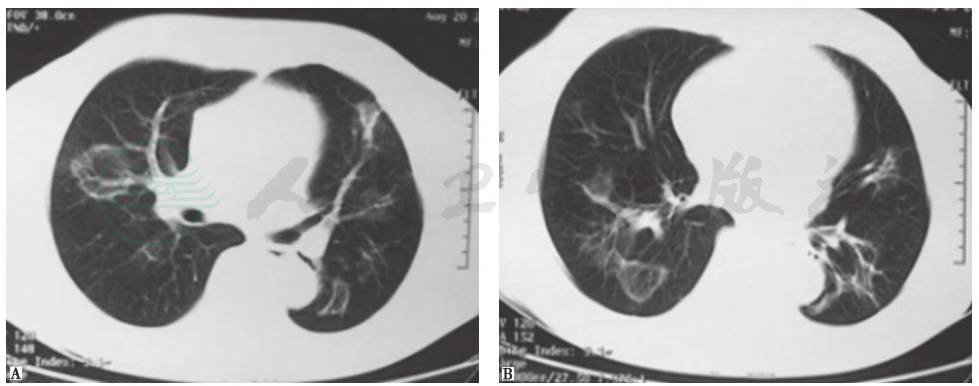

发病第4天,患者于当地医院就诊,胸部CT提示双肺多发结节样改变(图1)。

图1 发病第4天胸部CT表现

发病第32天,患者转至当地上级医院就诊,胸部CT提示病变较前加重,可见双肺多发大小不一的结节影,部分呈反晕环状,边缘尚清(图2)。

图2 发病第32天胸部CT表现